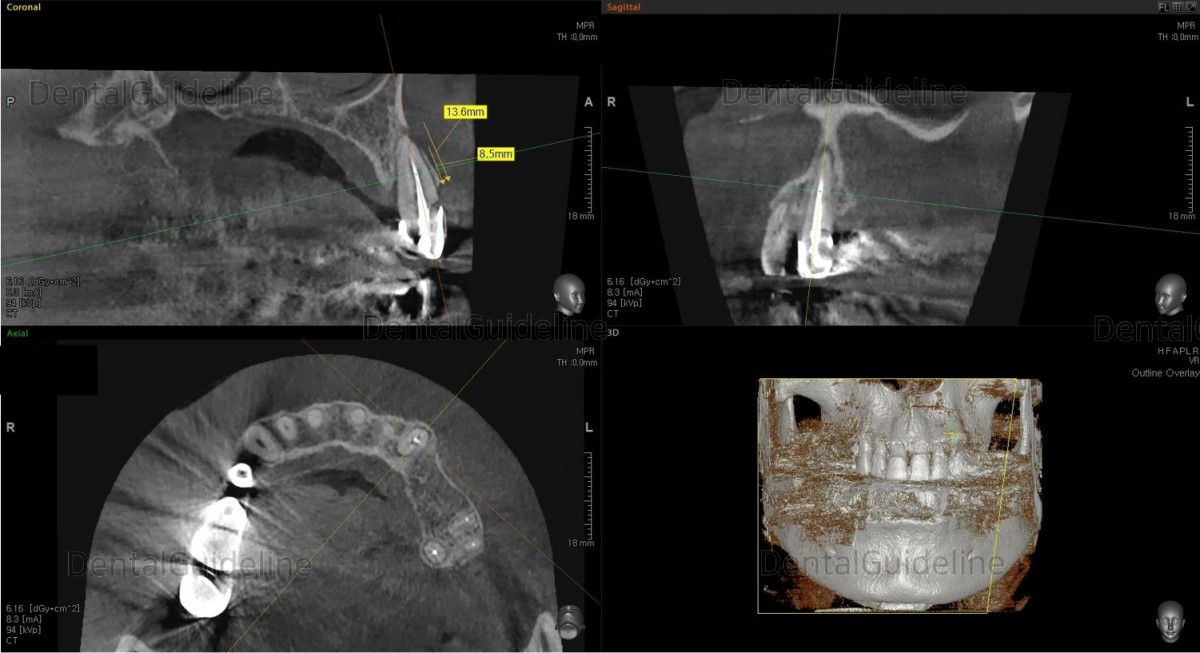

CBCT